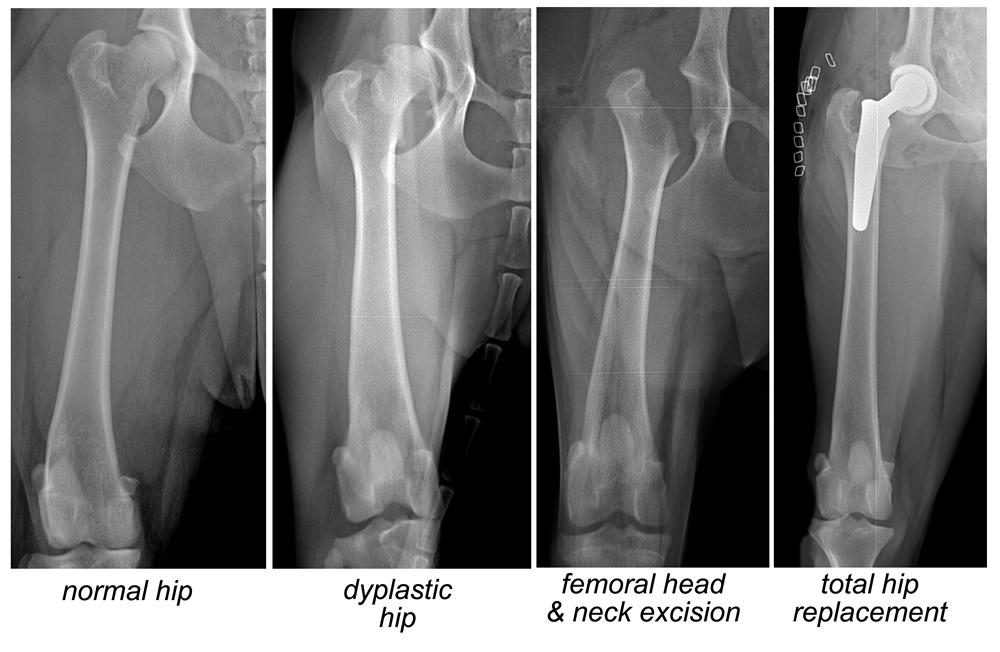

外科手術亦是其中一種治療方法。獸醫會根據狗狗的情況採用不同的手術。三處骨盆骨切開手術、全髖關節置換、股骨頭切除術。三處骨盆骨切開手術通常在少於12個月大、沒有患上退化性關節炎或症狀輕微的狗狗身上進行。全髖關節置換和股骨頭切除術通常在成年狗隻身上進行。

但是動手術與否,或選擇哪種手術,都需要由獸醫詳細檢查,根據體重、年齡、品種、病症的嚴重程度、手術的難度和術後恢復等等而定。